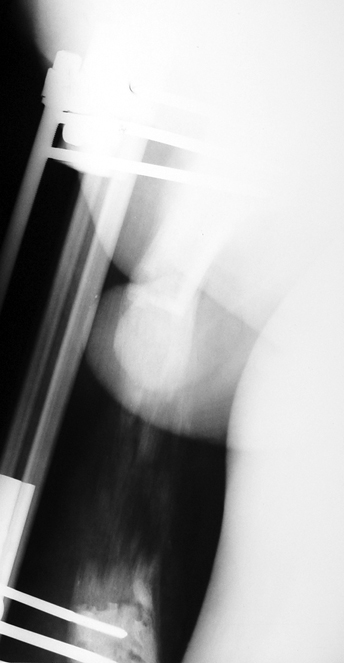

Chronic osteomyelitis leads to necrosis of bone and soft tissues. Dead bone is a nidus which hosts pathogenous microorganisms. Defence mechanisms of the host is usually not in optimum condition to deal with microorganisms. Antibiotics can’t reach the infection site because blood flow is disrupted. For these reasons, dead bone has to be completely removed by radical debridement.

Appropriate radical debridement necessitates excision of all necrotic bone and soft tissues, and frequently causes instability at the involved extremity. The remaining bone and soft tissue defect has to be fixed and reconstructed. The distraction osteogenesis method of Ilizarov is used successfully for achievement of union, correction of the deformity, elimination of limb length inequality and reconstruction of segmental bone defects.